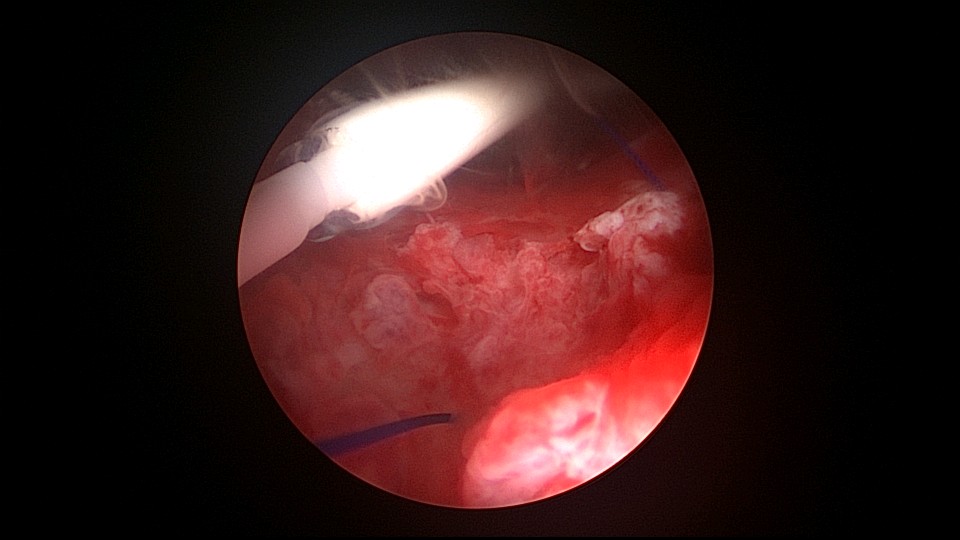

患者42,G3P1,顺产1次。子宫腺肌症伴腺肌瘤,逐渐加重的痛经,2024年11月起皮下注射亮丙瑞林3个周期,出现潮热出汗症状。2025年4月,要求放置曼月乐环并固定,子宫后位,宫深9cm,宫腔上段右侧粘连,宫腔下段宽大。4-0不可吸收线将曼月乐缝合固定于宫腔上段后壁,缝线上靠近曼月乐间距1cm左右打3个结,缝合1针,将1个线结拉过缝合处肌层,利用子宫肌层线结卡压固定曼月乐,避免打结推结。术后多次复查B超,曼月乐位置正常,环顶端距宫底1.6cm。